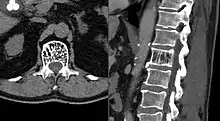

Axial and sagittal CT views of a vertebral hemangioma | |

On computed tomography (CT) or radiograph, VHs can cause rarefaction with vertical striations (often referred to as corduroy pattern) or a coarse honeycomb appearance. A polka-dot appearance on CT scan represents a cross-section of reinforced trabeculae.[11][13] CT best defines the bony architecture and is the best diagnostic imaging method.[14]